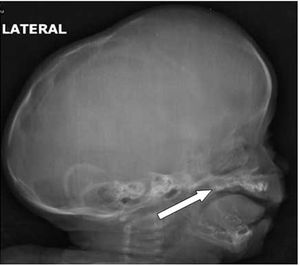

Case History: 3-month-old child with abnormal growth of head size.